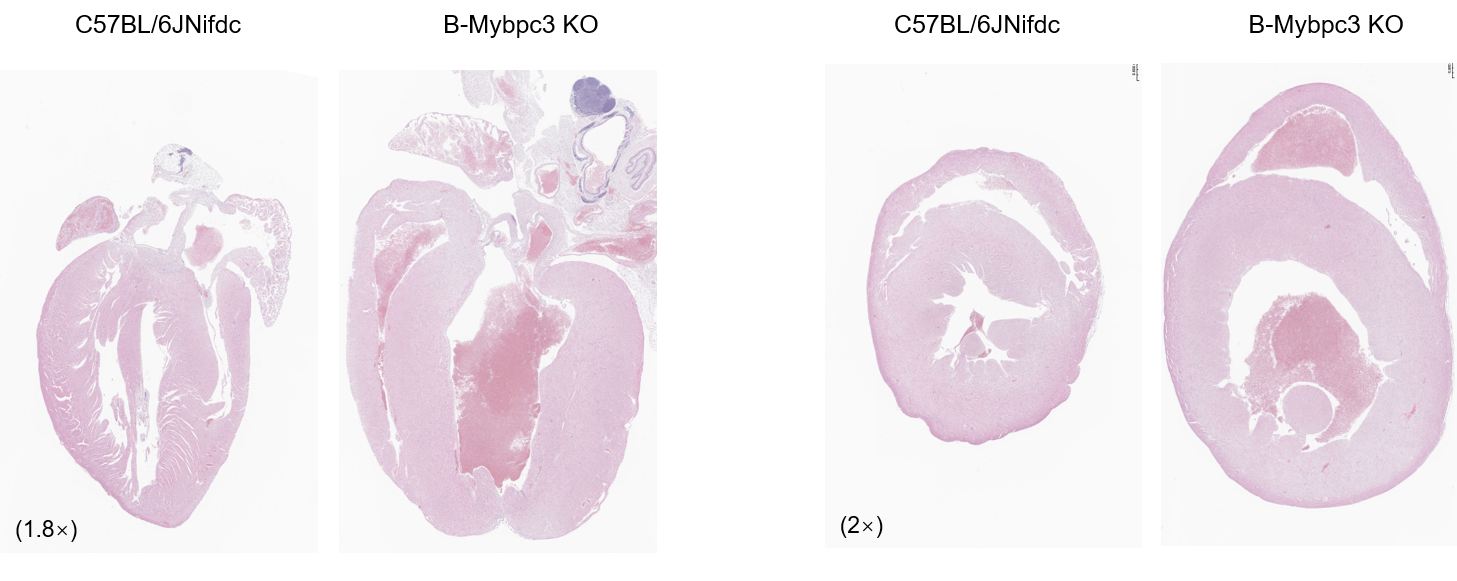

Histopathological analysis of heart tissue in homozygous B-Mybpc3 KO mice. Heart was collected from wild-type C57BL/6JNifdc mice (+/+) (male, 7-week-old, n=2) and homozygous B-Mybpc3 KO mice (-/-) (male, 7-week-old, n=2) and H&E-staining were performed. (A) Longitudinal section. (B) Transverse section of the heart. Results showed cardiac enlargement, ventricular wall thickening, and ventricular dilatation in homozygous B-Mybpc3 KO mice but not in wild-type mice, and the pathological changes in heart tissue is consistent with the characteristics of hypertrophic cardiomyopathy.